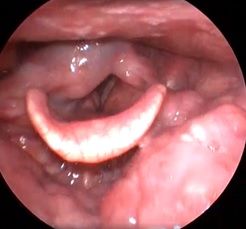

Клинический пример №1. Удаление папиллома правой голосовой складки с использованием СО-2 лазера.

После операции воспалительные проявления со стороны голосовой складки едва заметны.

Рис 1А Папиллома правой голосовой складки. До операции.

Рис 1Б. Папиллома правой голосовой складки. 1 сутки после операции

Рис 1В. Папиллома правой голосовой складки. 7 сутки после операции